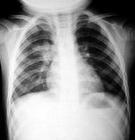

♥大肠埃希杆菌肺炎

大肠埃希杆菌(Escherichia co1i,又称大肠杆菌)肺炎近年来明显增加,是引起社区获得性革兰阴性杆菌肺炎的仅次于肺炎克雷白杆菌的第二位常见病原菌,占革兰阴性杆菌肺炎的12%~45%,占全部肺炎病原的2.0%~3.3%。它是医院内获得性肺炎的主要病原菌之一其发病率为4.2~9.0/1万,占革兰阴性杆菌肺炎的9.0%~15.0%20世纪60年代该病的病死率高达60%,80年代后明显下降,有报道为29%。